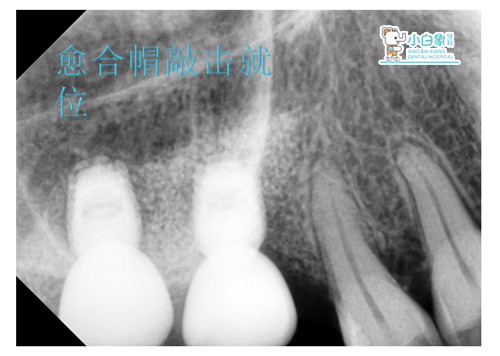

检查:口内查:16 17 愈合基台在。

检查:口内查:16 17愈合基台存。

治疗过程:16 17去除愈合基台后,敲击就位修复基台,试戴全瓷冠,粘结。